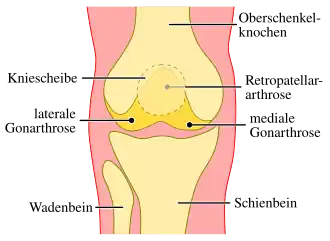

Betroffene Gelenkabschnitte

Das Kniegelenk besteht aus drei Gelenkabschnitten, die allesamt (Pangonarthrose) oder einzeln betroffen sein können. Bei Verschleiß im Kniescheibengelenk (Femoropatellargelenk) wird oft von einer Retropatellararthrose (Arthrose im Kniegelenk, hinter der Kniescheibe[1]) gesprochen. Ist das innere oder mediale Kompartiment des Femorotibialgelenks betroffen, liegt eine mediale Gonarthrose, oder bei oft gleichzeitiger O-Bein-Fehlstellung eine Varus-Gonarthrose vor. Die Arthrose des äußeren oder lateralen femorotibialen Kompartiments ist die laterale Gonarthrose, oder bei gleichzeitiger X-Bein-Fehlstellung die Valgus-Gonarthrose.